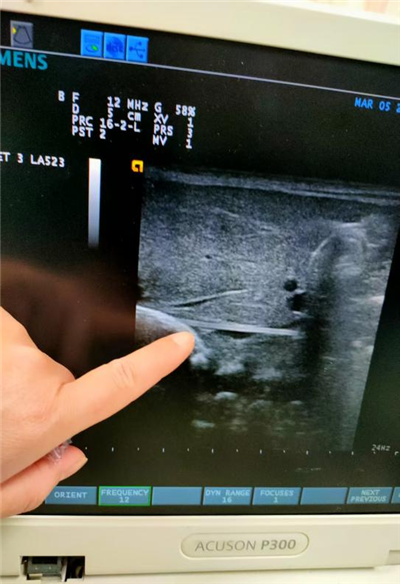

(我院新生儿科医生为患儿进行超声定位)